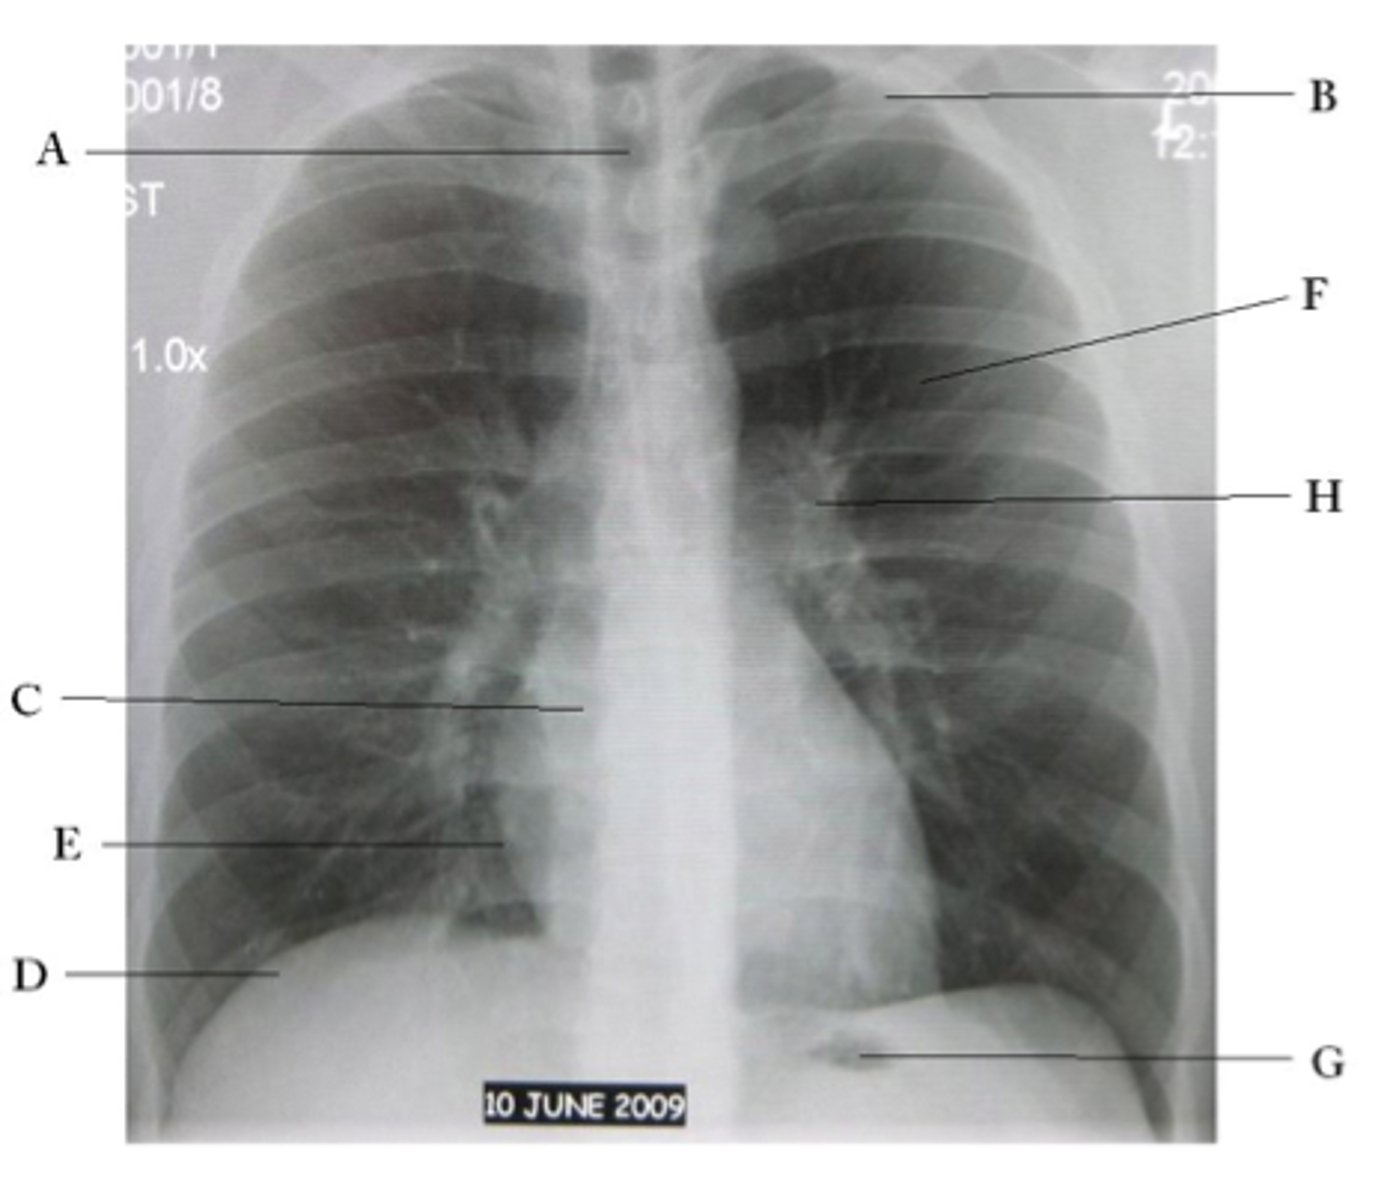

A

trachea

B

Clavicle

C

Right atrium

D

Diaphragm

E

Cardiophrenic angle

F

left upper lobe

G

gastric bubble

H

Left hilum